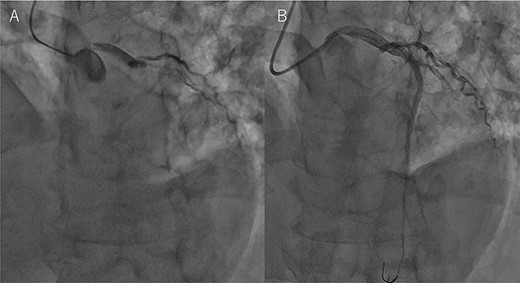

An Asian male in his 60s complained of sudden chest pain and was referred to a regional hospital. Electrocardiography showed massive ST-elevation in V1-4, and emergency coronary angiography revealed occlusion of the left anterior descending (LAD) artery (Fig. 1a). PCI was successfully performed (Fig. 1b), and IABP was inserted. Maximum value of creatine-kinase was 10 080Â U/l, and his left ventricular function was severely impaired with an ejection fraction of 30%. High dosage of catecholamine was administrated and his hemodynamic status gradually recovered; however, he fell into profound cardiogenic shock on post PCI Day 6. Chest X-ray showed significant cardiomegaly (Fig. 2a), and trans-thoracic echocardiography revealed cardiac tamponade.

Coronary angiography findings. (A) Pre PCI, the LAD artery was completely occluded. (B) Post PCI, the LAD was recanalized.